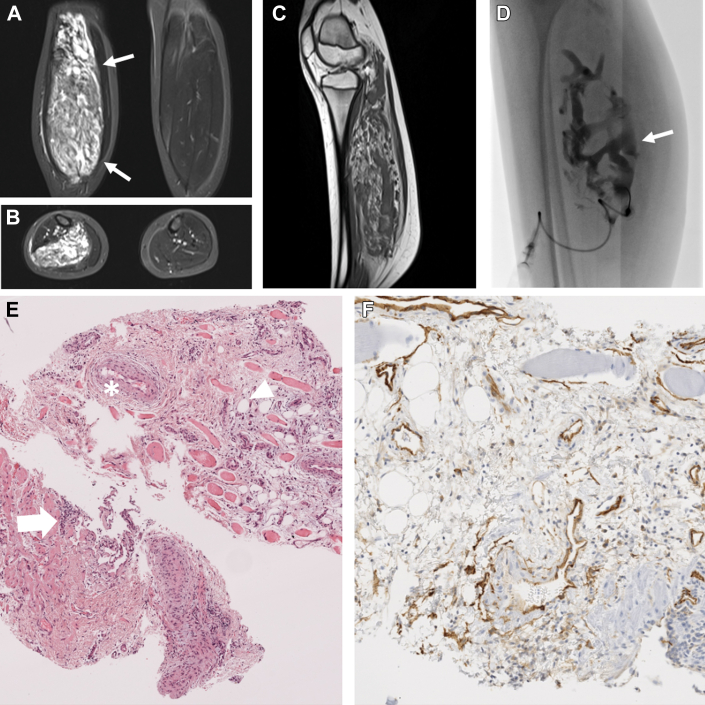

Magnetic resonance imaging revealed a vascularized lesion with interposed fatty tissue located in the flexor musculature (Figures 1A and 1B) and diffuse dysplastic venous channels. In contrast to common venous malformations, in which the T2 signal is typically similar to fluid signal and relatively homogeneous, the T2 signal in FAVA is less hyperintense than in common venous malformation and far more heterogeneous because of the presence of fibro-fatty infiltration (Figure 1C). Several dilated, dysplastic veins in the sense of a VM were seen in the entire affected musculature, additionally shown during diagnostic phlebography (Figure 1D). Due to the low-flow and consecutive stasis of the blood within the malformation, formation of fluid-fluid levels could be observed. In addition, a large thrombus in a dilated, dysplastic vein was detected. The contrast-enhanced magnetic resonance angiography showed a complete enhancement of the VM component in the left leg with pooling of the contrast agent.

Figure 1.

Multimodal Imaging and Histopathologic Findings of FAVA

(A and B) Coronal and axial T2-weighted fat-suppressed magnetic resonance images showing an intramuscular vascular lesion with clearly interposed hyperintense fatty tissue, more than is usual in a normal venous malformation. (C) Sagittal T1-weighted magnetic resonance image with typical presentation of a fibro-adipose vascular anomaly (FAVA) called the black and white "salt and pepper pattern," caused by the neighboring fatty tissue and connective tissue. (D) Plain angiography image presents an extensive network of dilated, dysplastic venous channels forming the venous malformation part (arrow). (E) Overview tissue core in hematoxylin and eosin stain showing infiltrating vascularized fibro-adipose soft tissue (arrowhead) between skeletal muscle fibers and thick-walled venous vessels (asterisk) as well as several lymphoid aggregates (arrow). (F) CD34 immunostaining showing CD34 co-expression in the endothelium.

In addition to diagnostic phlebography (Figure 1D) for mapping of the deep venous system, an image-guided lesional biopsy was performed to secure the diagnosis and gain additional molecular information. Histopathologic examination showed infiltrating vascularized fibro-adipose soft tissue between skeletal muscle fibers and thick-walled, muscularized venous channels (Figure 1E). CD34 immunostaining revealed CD34 co-expression in the endothelium (Figure 1F), sometimes aberrantly co-expressed with podoplanin (not shown). Furthermore, aggregates of lymphocytes and perivascular mononuclear cell infiltrate were noted on hematoxylin and eosin staining. Pyrosequencing of the PIK3CA gene (exons 8, 10, and 21) revealed an activating PIK3CA mutation in exon 21 of the PIK3CA gene. With display of typical histomorphologic and molecular pathologic characteristics, the suggested diagnosis of FAVA was confirmed.